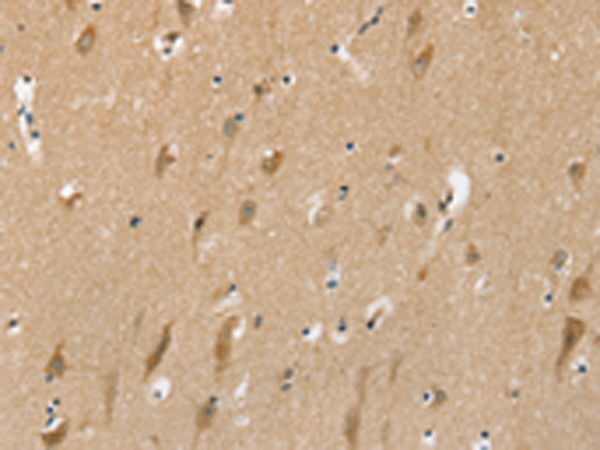

分类: 科研抗体货号: P12202别名: NCX3应用: IHC反应种属: Human, Rat